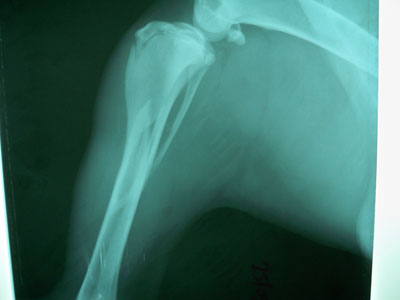

Γιαπωνέζικο mastif 11 μηνών με πρόσφατο λοξό κάταγμα στο άνω / τρίτο της διάφυσης της δεξιάς κνήμης και περόνης.